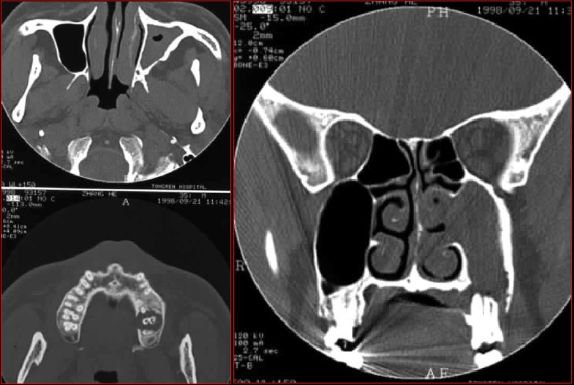

鼻窦炎—破溃入口腔

牙源性鼻窦炎